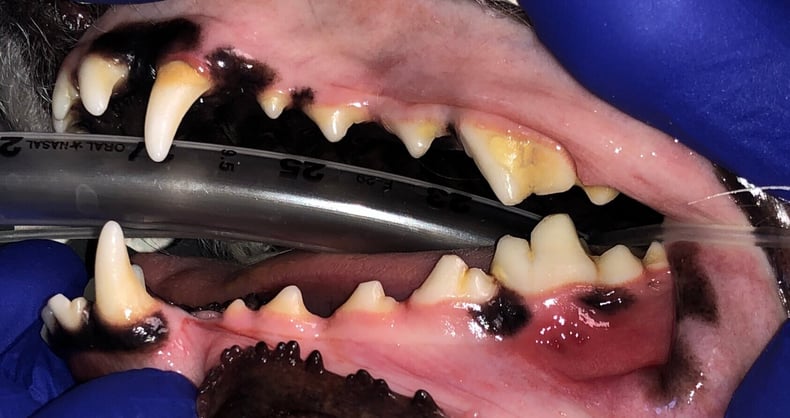

Below: Physical Picture of Initial Presentation